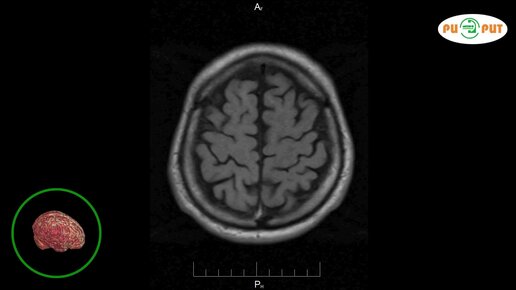

Как делают МРТ головного мозга